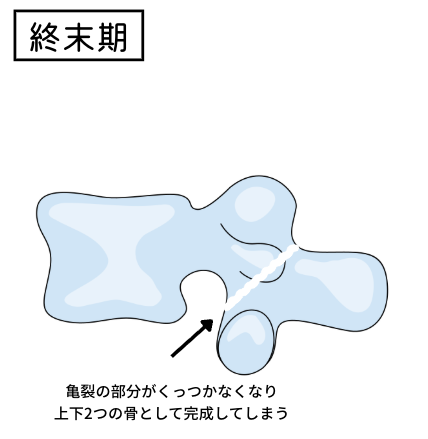

分離症には「初期」「進行期」「終末期」の3段階に分かれています。

最後の「終末期」は完全に骨が離れ、くっつかなくなった状態です。こうなると治療の考え方は大きく変わり、“骨をくっつける”という視点から“いかに安定させるか”に変わります。つまり、ストレッチや体幹トレーニングを基本としたケアを行い、様々な症状が出てこないよう気をつけて生活する必要があります。